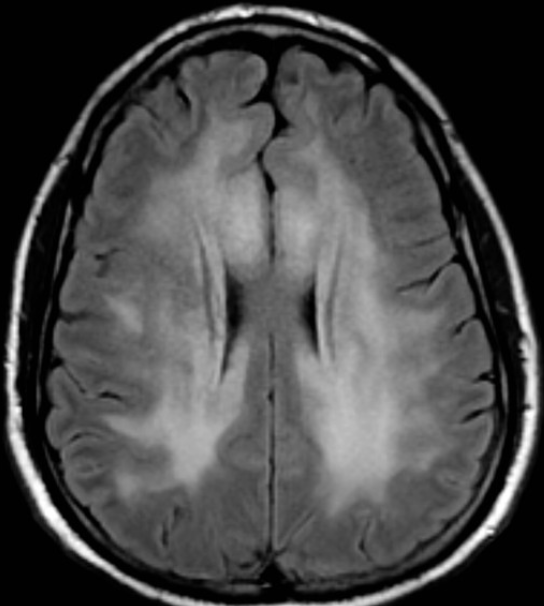

Imagem 3

A intoxicação por monóxido de carbono (CO)